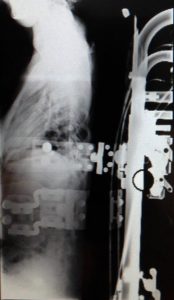

Radiografia lateral amb Spex

En utilitzar el els coixins i respatllers Spex, tant la cifosi com la retroversió s’han corregit, aconseguint un millor posicionament.